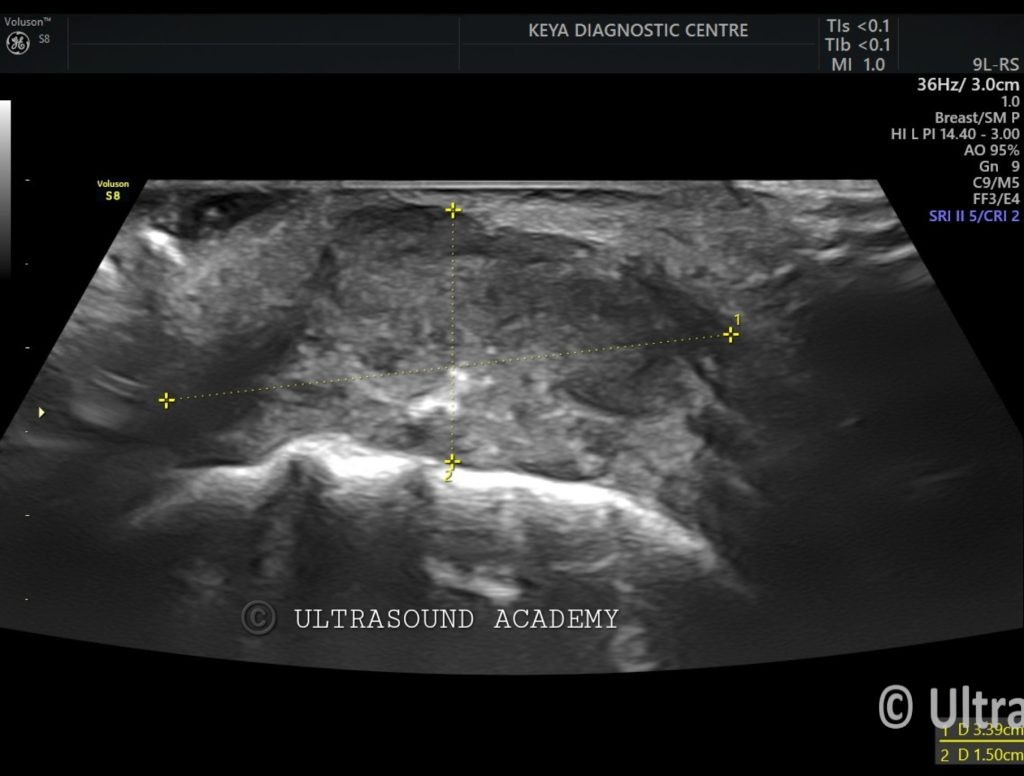

• Hypoechoic irregular mass measuring approximately Approx 1.5 cm in greatest dimension located in the left buccal mucosa.

• The mass shows heterogeneous echotexture with poorly defined borders, invading into the adjacent soft tissues.

• Also an ulcer with air foci seen as hyperechoic specks.